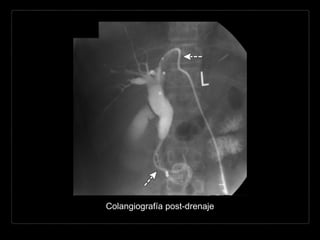

Colangiografía post-drenaje

• #138 Cholangiographic image, obtained by means of a transhepatic biliary drainage catheter (arrows) after percutaneous and endoscopic procedures for stone removal and stent placement, shows persistent ductal dilatation.